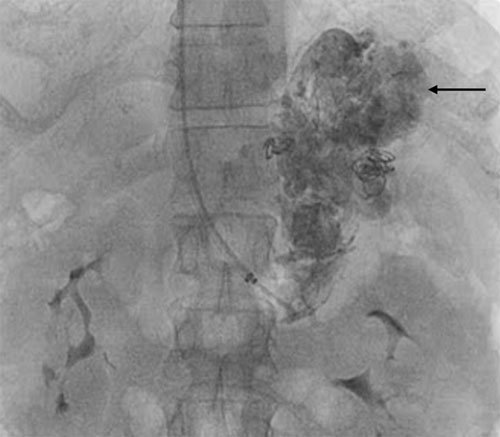

- Balloon-occluded retrograde transvenous obliteration (BRTO) has been introduced as a treatment method that aims to directly obliterate the GVA.

- The technical difficulty of BRTO relies on the anatomy of the afferent and draining veins of the GV.

- In most cases, there is a gastrorenal or gastrocaval shunt. In this situation under fluoroscopic guidance, a balloon catheter is inserted into the outlet of the gastrorenal or gastrocaval shunt through a sheath placed in the right femoral vein.

- Immediately afterward, venography is performed with an injection of 10–15 mL contrast medium via the inflated balloon catheter, and GV are slowly, intermittently, and completely filled with a sclerosant.